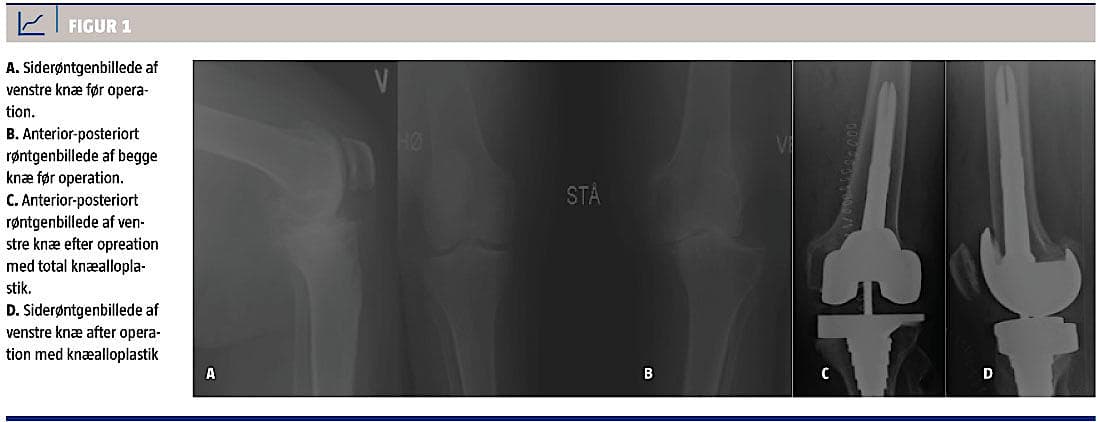

En røntgenoptagelse af venstre knæ viste udtalte artroseforandringer og subluksation (grad 4-5 ved Ahlbäcks klassifikation). Det højre knæ var radiologisk uden tegn til artrose (Figur 1A + B).

Patienten mobiliseredes senere samme dag og blev udskrevet efter fire dage. Et postoperativt taget røntgenbillede viste velplaceret knæalloplastik (Figur 1C + D). Man afsluttede behandlingen ved tomåneders ambulant kontrol, hvor der blev fundet god stilling og fin bevægelighed i knæet.